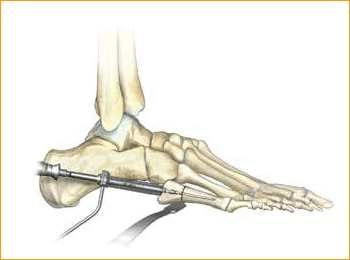

Jones Fracture Technique for 4.5 mm and 5.5 mm Headless Compression screws.

4. MEASURE DEPTH

Depth is measured from the exposed portion of the guide wire with the cannulated depth gauge.

5. ADVANCE GUIDE WIRE

After selecting the size, advance the guide wire approximately 5 mm to maintain distal pin fixation before drilling.

Caution: Make sure not to compromise distal joint surfaces when advancing the guide wire.

6. SOFT TISSUE GUIDE PLACEMENT

Place the soft tissue guide (the guide should be used throughout) over the guide wire and open the near cortex using the appropriate cannulated profile drill.

7. DRILL

Leaving the soft tissue guide in place, drill into the far fragment with the appropriate cannulated, long drill. Reference the markings on the drill to confirm desired depth.

Tip: The long drill is recommended to mitigate the effects of varying bone density and distraction upon screw insertion.